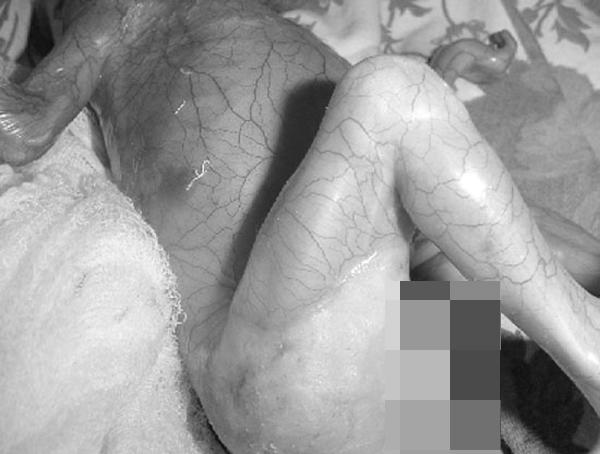

Em bé chào đời với hội chứng không có da hiếm gặp.

Toàn bộ cơ thể của em bé được bao phủ trong một lớp màng, có thể dễ dàng nhìn thấy từng mạch máu. Em bé cũng không có móng tay, tóc hay núm vú và khi chào đời chỉ nặng 1,02kg, chu vi vòng đầu là 26,5 cm. Thông thường, chu vi vòng đầu của trẻ sơ sinh nằm trong khoảng từ 33 cm đến 38 cm. Với tình trạng nghiêm trọng như vậy, bé được chăm sóc đặc biệt tại lồng ấp. Tuy nhiên, em bé không thể tiếp tục sự sống và qua đời chỉ sau 4 ngày được điều trị.

Theo các chuyên gia, việc em bé sinh ra không có làn da được gọi là hội chứng Aplasia cutis congenita - một tình trạng hiếm gặp với trẻ sơ sinh, có liên quan đến việc người mẹ sử dụng những loại thuốc không an toàn trong thai kỳ, đặc biệt là azathioprin.